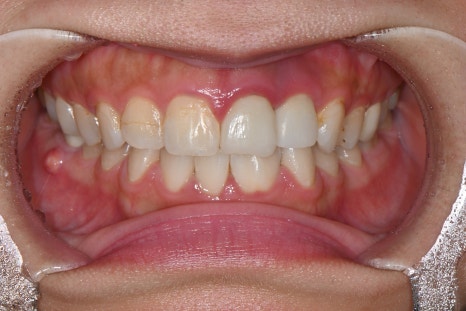

Right photo: “The existing prosthetics had different colors for each tooth and inconsistent shapes, making the front tooth line look uneven and unnatural.”

“The existing front teeth had been filled with old materials, and because the color and shape were all different, the front tooth line looked awkward when smiling.”